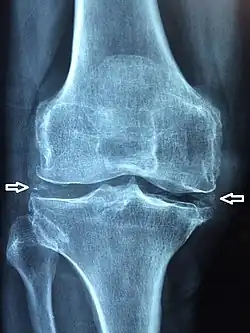

X-ray, CT, or other imaging usually shows accumulation of calcium within the joint cartilage, known as chondrocalcinosis. There can also be findings of osteoarthritis.[5][4] The white blood cell count is often raised.[4]

Medical imaging, consisting of x-ray, CT, MRI, or ultrasound may detect chondrocalcinosis within the affected joint, indicating a substantial amount of calcium crystal deposition within the cartilage or ligaments.[2] Ultrasound is a reliable method to diagnose CPPD.[8] Using ultrasound, chondrocalcinosis may be depicted as echogenic foci with no acoustic shadow within the hyaline cartilage[9] or fibrocartilage.[8] By x-ray, CPPD can appear similar to other diseases such as ankylosing spondylitis and gout.[2][4]